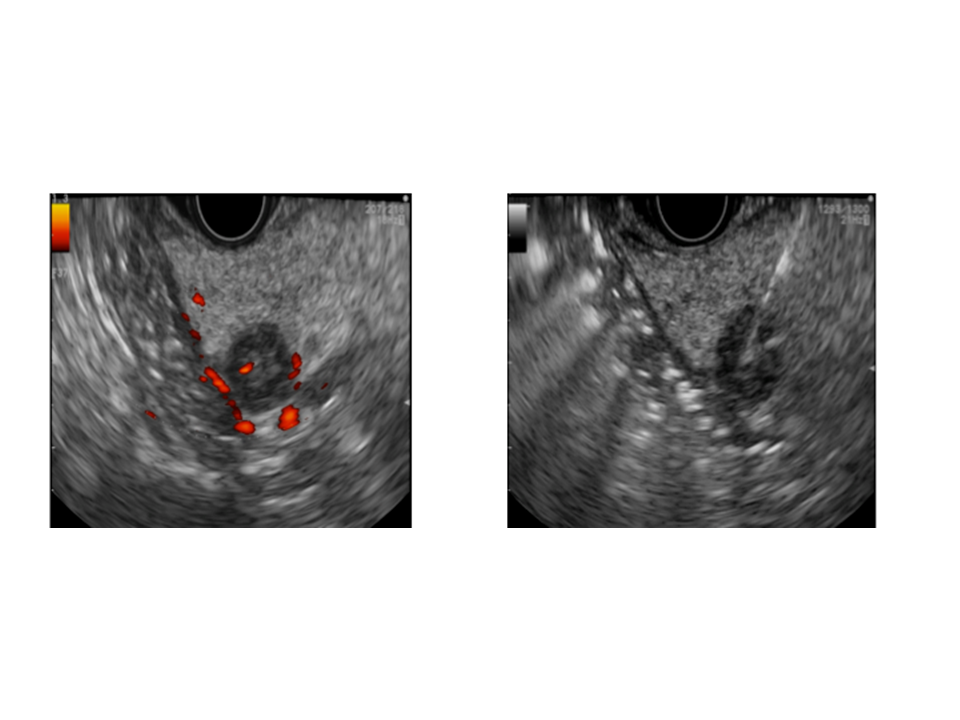

Image gauche : tumeur visible

Image droite : l'aiguille se place à l'intérieur de la tumeur

En pratique, le gastroentérologue-endoscopiste introduit par voie orale, un endoscope spécifique, l’échoendoscope à l’extrémité duquel se trouve une sonde d’échographie miniaturisée. Après repérage de la lésion au travers de la paroi intestinale, il introduit sous contrôle échographique une aiguille au cœur de la tumeur. Une fois en place, l’aiguille délivre un courant électrique qui va détruire la tumeur en une quinzaine de secondes, par radiofréquence. L’efficacité est immédiate.